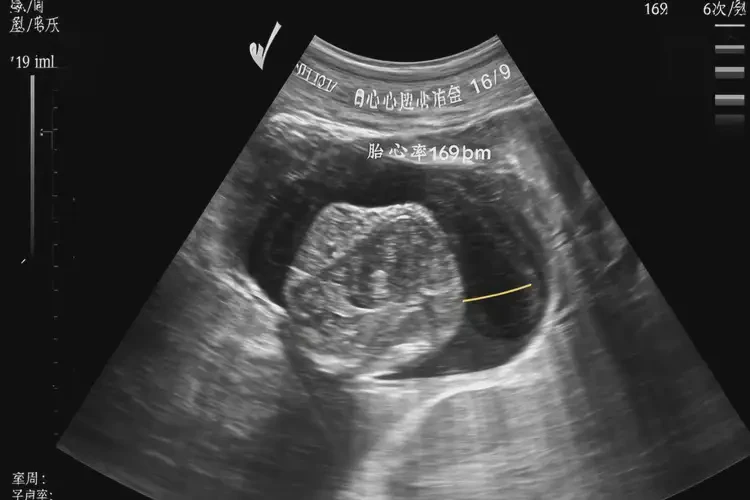

孕19周6天胎心率169還能保住嗎

胎心率169次/分鐘在孕19周6天屬于正常范圍,胎兒通常可以保住。

胎心率是評估胎兒健康狀況的重要指標之一。在孕19周6天時,胎兒的正常胎心率范圍為140-170次/分鐘。胎心率為169次/分鐘處于正常范圍內(nèi),這表明胎兒的心臟功能正常,沒有明顯的異常情況。

孕19周6天胎心率169還能保住嗎(圖1)